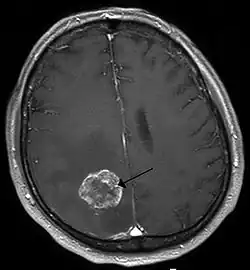

Imaging

Medical imaging plays a central role in the diagnosis of brain tumors. Early imaging methods – invasive and sometimes dangerous – such as pneumoencephalography and cerebral angiography have been replaced by non-invasive, high-resolution techniques, especially magnetic resonance imaging (MRI) and computed tomography (CT) scans.[42] MRI with contrast enhancement is the preferred imaging test in the diagnosis of brain tumors.[24][43] Glioblastomas usually enhance with contrast on T1 MRI weighted MRI imaging, and on T2 with FLAIR imaging showing hyperintense cerebral edema.[24] Low grade gliomas are usually hypointense on T1 MRI, and hyperintense with T2 with FLAIR MRI. Meningiomas are usually homogenously enhanced with dural thickening on MRI.[24]